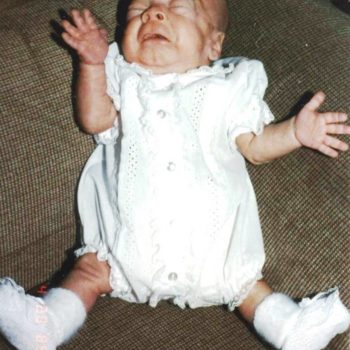

Fallen Socks Sign of Lax Skin – Dermatosparaxis

Please click to enlarge.

Note what signs you see.

I (W. Wertelecki, M.D.) see the photograph of the subject illustrated in the Gallery.

PERSPECTIVE: Please, see the principles of identification of “new” human disorders and related video of this patient.